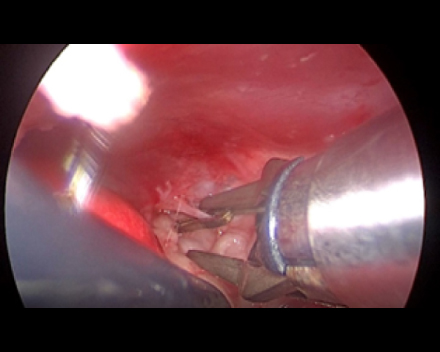

胸腔鏡で覗くと胸管がキレイに見えます(黒矢印)。

これを鉗子で丁寧に剥離していきます